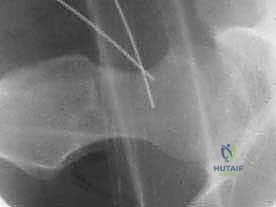

- الأشعة السينية (X-rays): لتقييم شكل العظام، قياس "زاوية ألفا" (Alpha Angle)، وتحديد وجود نتوءات الكامة أو الكماشة.

- الأشعة المقطعية الثلاثية الأبعاد (3D CT Scan): للتخطيط الجراحي الدقيق قبل العملية.